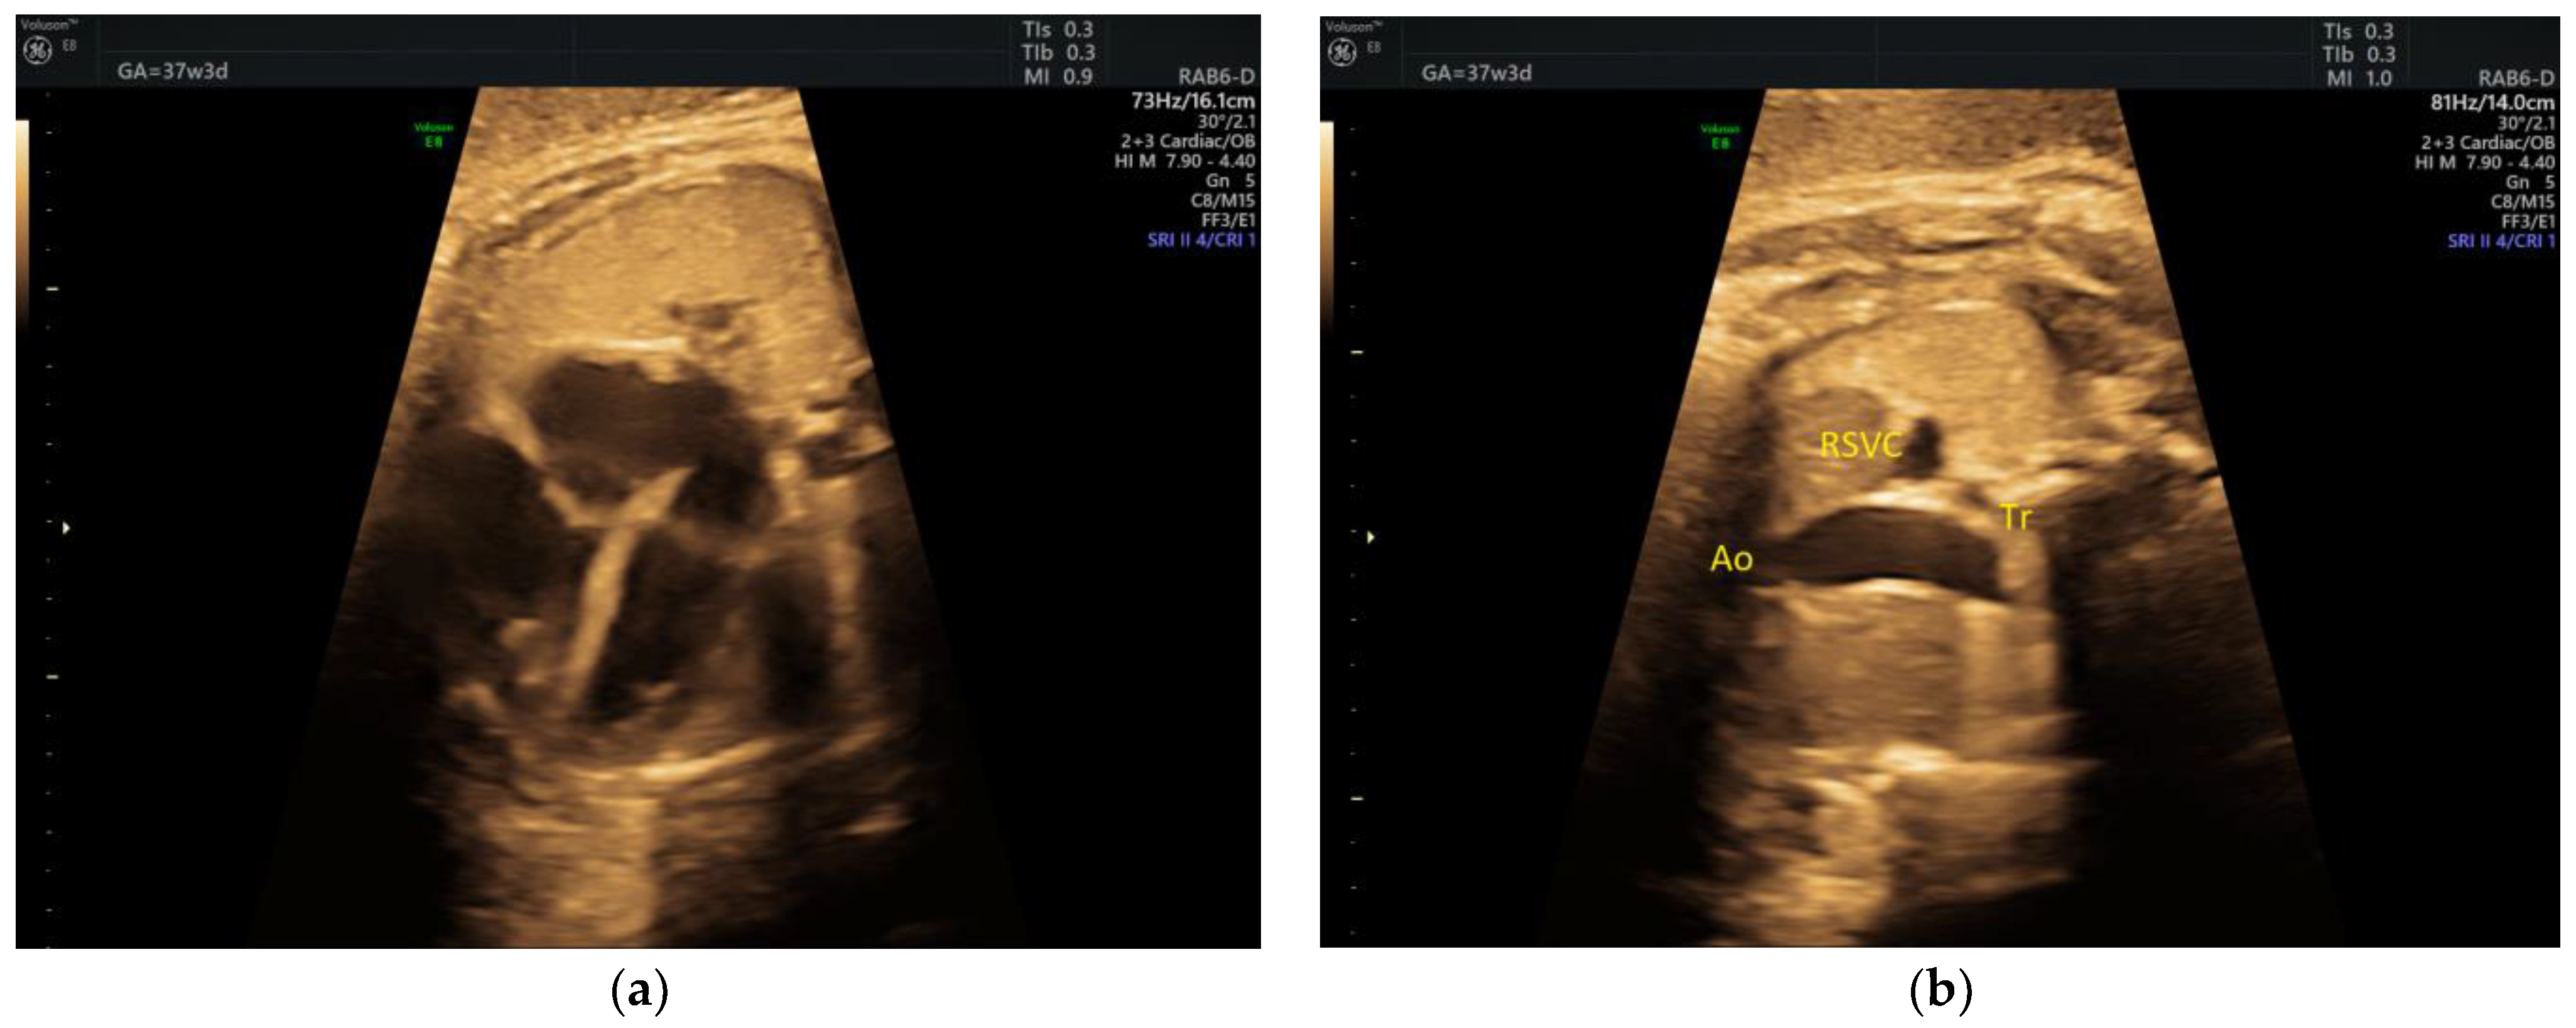

| DAA | 1 | Tortuous DA at 20 w + late FGR | - | 3VT | + | 0 | 0 | 1 | 1/1 |